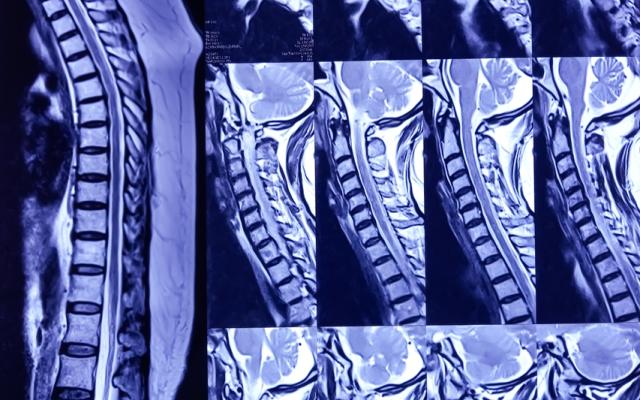

Het niet onderkennen van een wervelfractuur bij een traumapatiënt kan ernstige gevolgen hebben. Daarom wordt bij veel patiënten radiografisch onderzoek van de cervicale wervelkolom (X-CWK) verricht, ook als de voorafkans op een fractuur laag lijkt. Het aanvragen van een X-CWK bij een geselecteerd deel van deze groep zou een aanzienlijke…